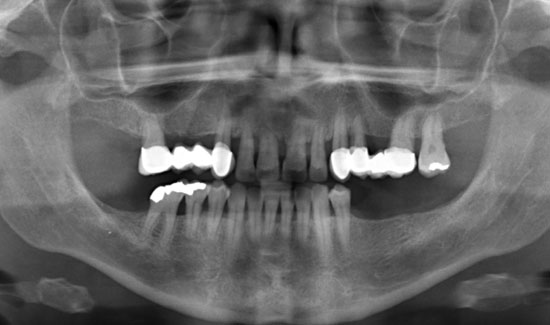

Fig. 1: Orthopantomogram

We are reporting on the successful treatment of an advanced case of Parodontitis marginalis profunda in the frontal area of the upper jaw of a 42-year old female patient with local application of ozone gas with the Prozone of W&H. Svea Baumgarten, Dr. med. dent., M Sc, accredited implantologist shares her experiences with ozone treatment.

The patient introduced herself at our practice, inquiring about preserving the front teeth of her upper jaw, which were suffering from chronic periodontitis. We discovered general formation of pockets

(> 10 mm), spontaneous bleeding and a degree of tooth mobility of 2/3, i.e. the teeth were candidates to be extracted. As an interim solution (it was a public holiday) until restoration could take place, we offered local ozone gas treatment.